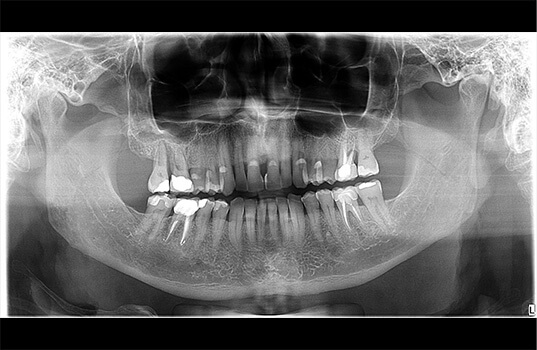

A Radiografia Panorâmica é uma radiografia de boca que fornece uma visão ampla dos dentes, mandíbula e maxila. É usada na odontologia para ajudar a identificar problemas dentários, como cáries, infecções, fraturas e outros problemas ósseos. Além disso, a Radiografia Panorâmica também pode ser usada para planejar tratamentos dentários, como a colocação de próteses e implantes dentários, como também para avaliar o desenvolvimento de tratamentos já realizados.

Na Radiografia Panorâmica, o paciente é posicionado na máquina de Raio-X e precisa ficar parado por alguns segundos enquanto a máquina faz a imagem. A imagem resultante mostra uma visão ampla da boca, mandíbula e maxila, permitindo aos dentistas visualizarem as estruturas ósseas e dentárias de uma só vez.